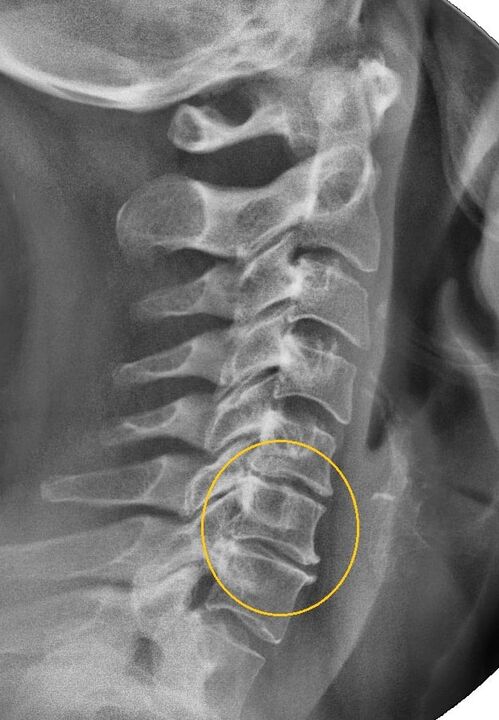

Diagnostiko-prozedurarik informatzaileena erradiografia da. 1. graduko patologiak 1. edo 2. etapa erradiologikoari dagozkio. Lortutako irudiek gaixotasunaren seinale tipikoak ikusten dituzte.

| 1. mailako osteokondrosi zerbikalaren X izpien faseak | Zeinu bereizgarriak |

|---|---|

| 1. etapa | Aldaketa txikiak bizkarrezurraren kurbaduran zerbikal eskualdean, segmentu bati edo gehiagori eragiten diote |

| 2. etapa | Orno arteko diskoen loditze arina, prozesu uncinateen deformazioa, lordosia zuzentzea, hezur-egituren hazkunde txikiak |